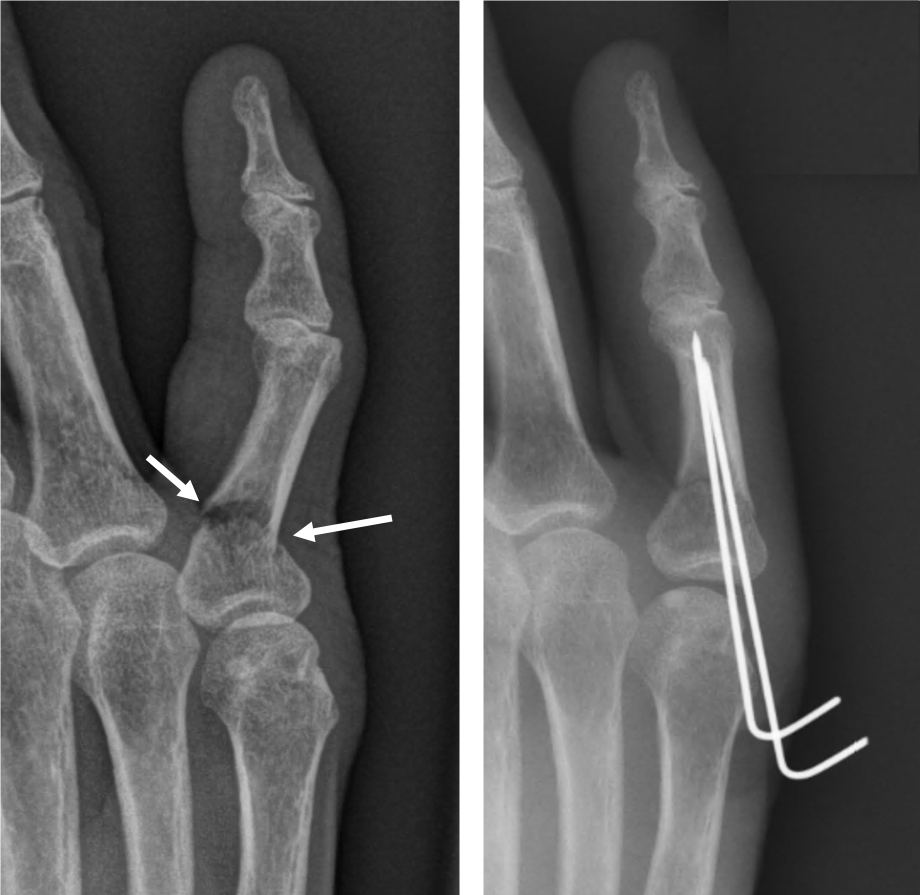

발가락 골절 수술 치료

- 적용 시기: 복합 골절, 압박 골절, 뼈 조각이 여러 개로 나뉜 경우처럼 깁스나 스플린트만으로 회복이 어려운 경우.

- 회복 기간: 수술 후에도 2~4주 이상의 안정기가 필요하며, 이후에는 재활 운동이 필수로 따라옵니다.

- 치료 방식: 핀을 박거나 금속판을 대는 방법을 사용합니다. 골절 부위를 정확히 정렬하고 뼈가 잘못 붙지 않도록 하는 것이 핵심입니다.

- 핀 고정 수술

- 뼈가 복합적으로 부러지거나, 어긋나서 그대로 붙으면 기능에 치명적 문제가 예상되는 경우에는 핀이나 금속판을 삽입하는 수술을 진행합니다.

- 수술 후에는 손가락 움직임을 최소화하고, 적절한 시점에 재활 운동을 시작해야 합니다.